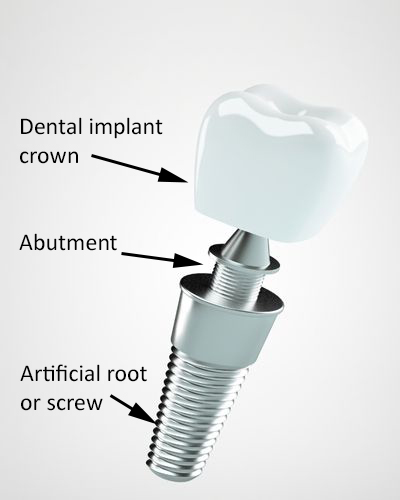

After a dentist prepares your teeth for porcelain veneers, you cannot have them removed and return to your natural teeth, which would increase sensitivity. You will need some type of cosmetic dentistry to protect your teeth, and veneers are less invasive than dental crowns.